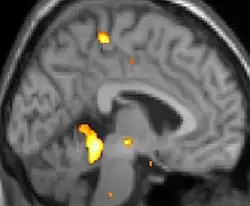

| La tomographie par émission de positons (TEP) montre les zones du cerveau étant activées durant la douleur | ||

Les images par tomographie à émission de positron indiquent les régions du cerveau qui sont activées lors de la douleur, par rapport aux périodes sans douleur. Elles montrent les régions du cerveau qui sont toujours actives durant la douleur en jaune/orange (appelé "matrice-douleur"). La zone au centre (dans les trois vues) est spécifiquement activée uniquement pendant la crise. Les photos sur la ligne du bas (effectuées par VBM) montrent les différences structurelles entre les patients souffrant d'AVF et des personnes saines : seulement une partie de l'hypothalamus est différente[50],[51].